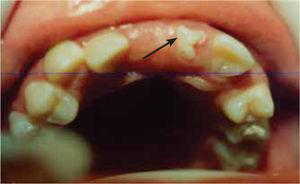

En el examen clínico intraoral se observa una dentición permanente con tejidos blandos normales, y caries dental en el segundo premolar y primer molar superior izquierdo, falta de erupción del incisivo central superior derecho y del canino superior izquierdo, presencia de un diente superior izquierdo semierupcionado con malformación y malposición dentaria. Su estudio radiográfico refiere la presencia de dos dientes supernumerarios en el arco superior, localizados en la línea media, uno invertido, (sin erupcionar) y el otro con malposición y malformación dentaria (semierupcionado); los dos centrales permanentes retenidos (Figuras 1y2).

El tratamiento consiste en la obturación de los dientes cariados y la extracción quirúrgica de los dientes SN. Al levantamiento del colgajo se comprueba la posición invertida del diente SN derecho y la presencia de una anomalía en su forma «conocida como perla del esmalte» y en el SN izquierdo su forma irregular; existe retención de los incisivos centrales permanentes con desplazamiento. Posteriormente se procede a la extracción quirúrgica de los dos dientes supernumerarios y se ligan los dientes permanentes para su tracción y alineamiento con tratamiento de ortodoncia, se sutura el colgajo. Se remueven los puntos de sutura a los ocho días. Su pronóstico fue favorable (Figuras 3a6)